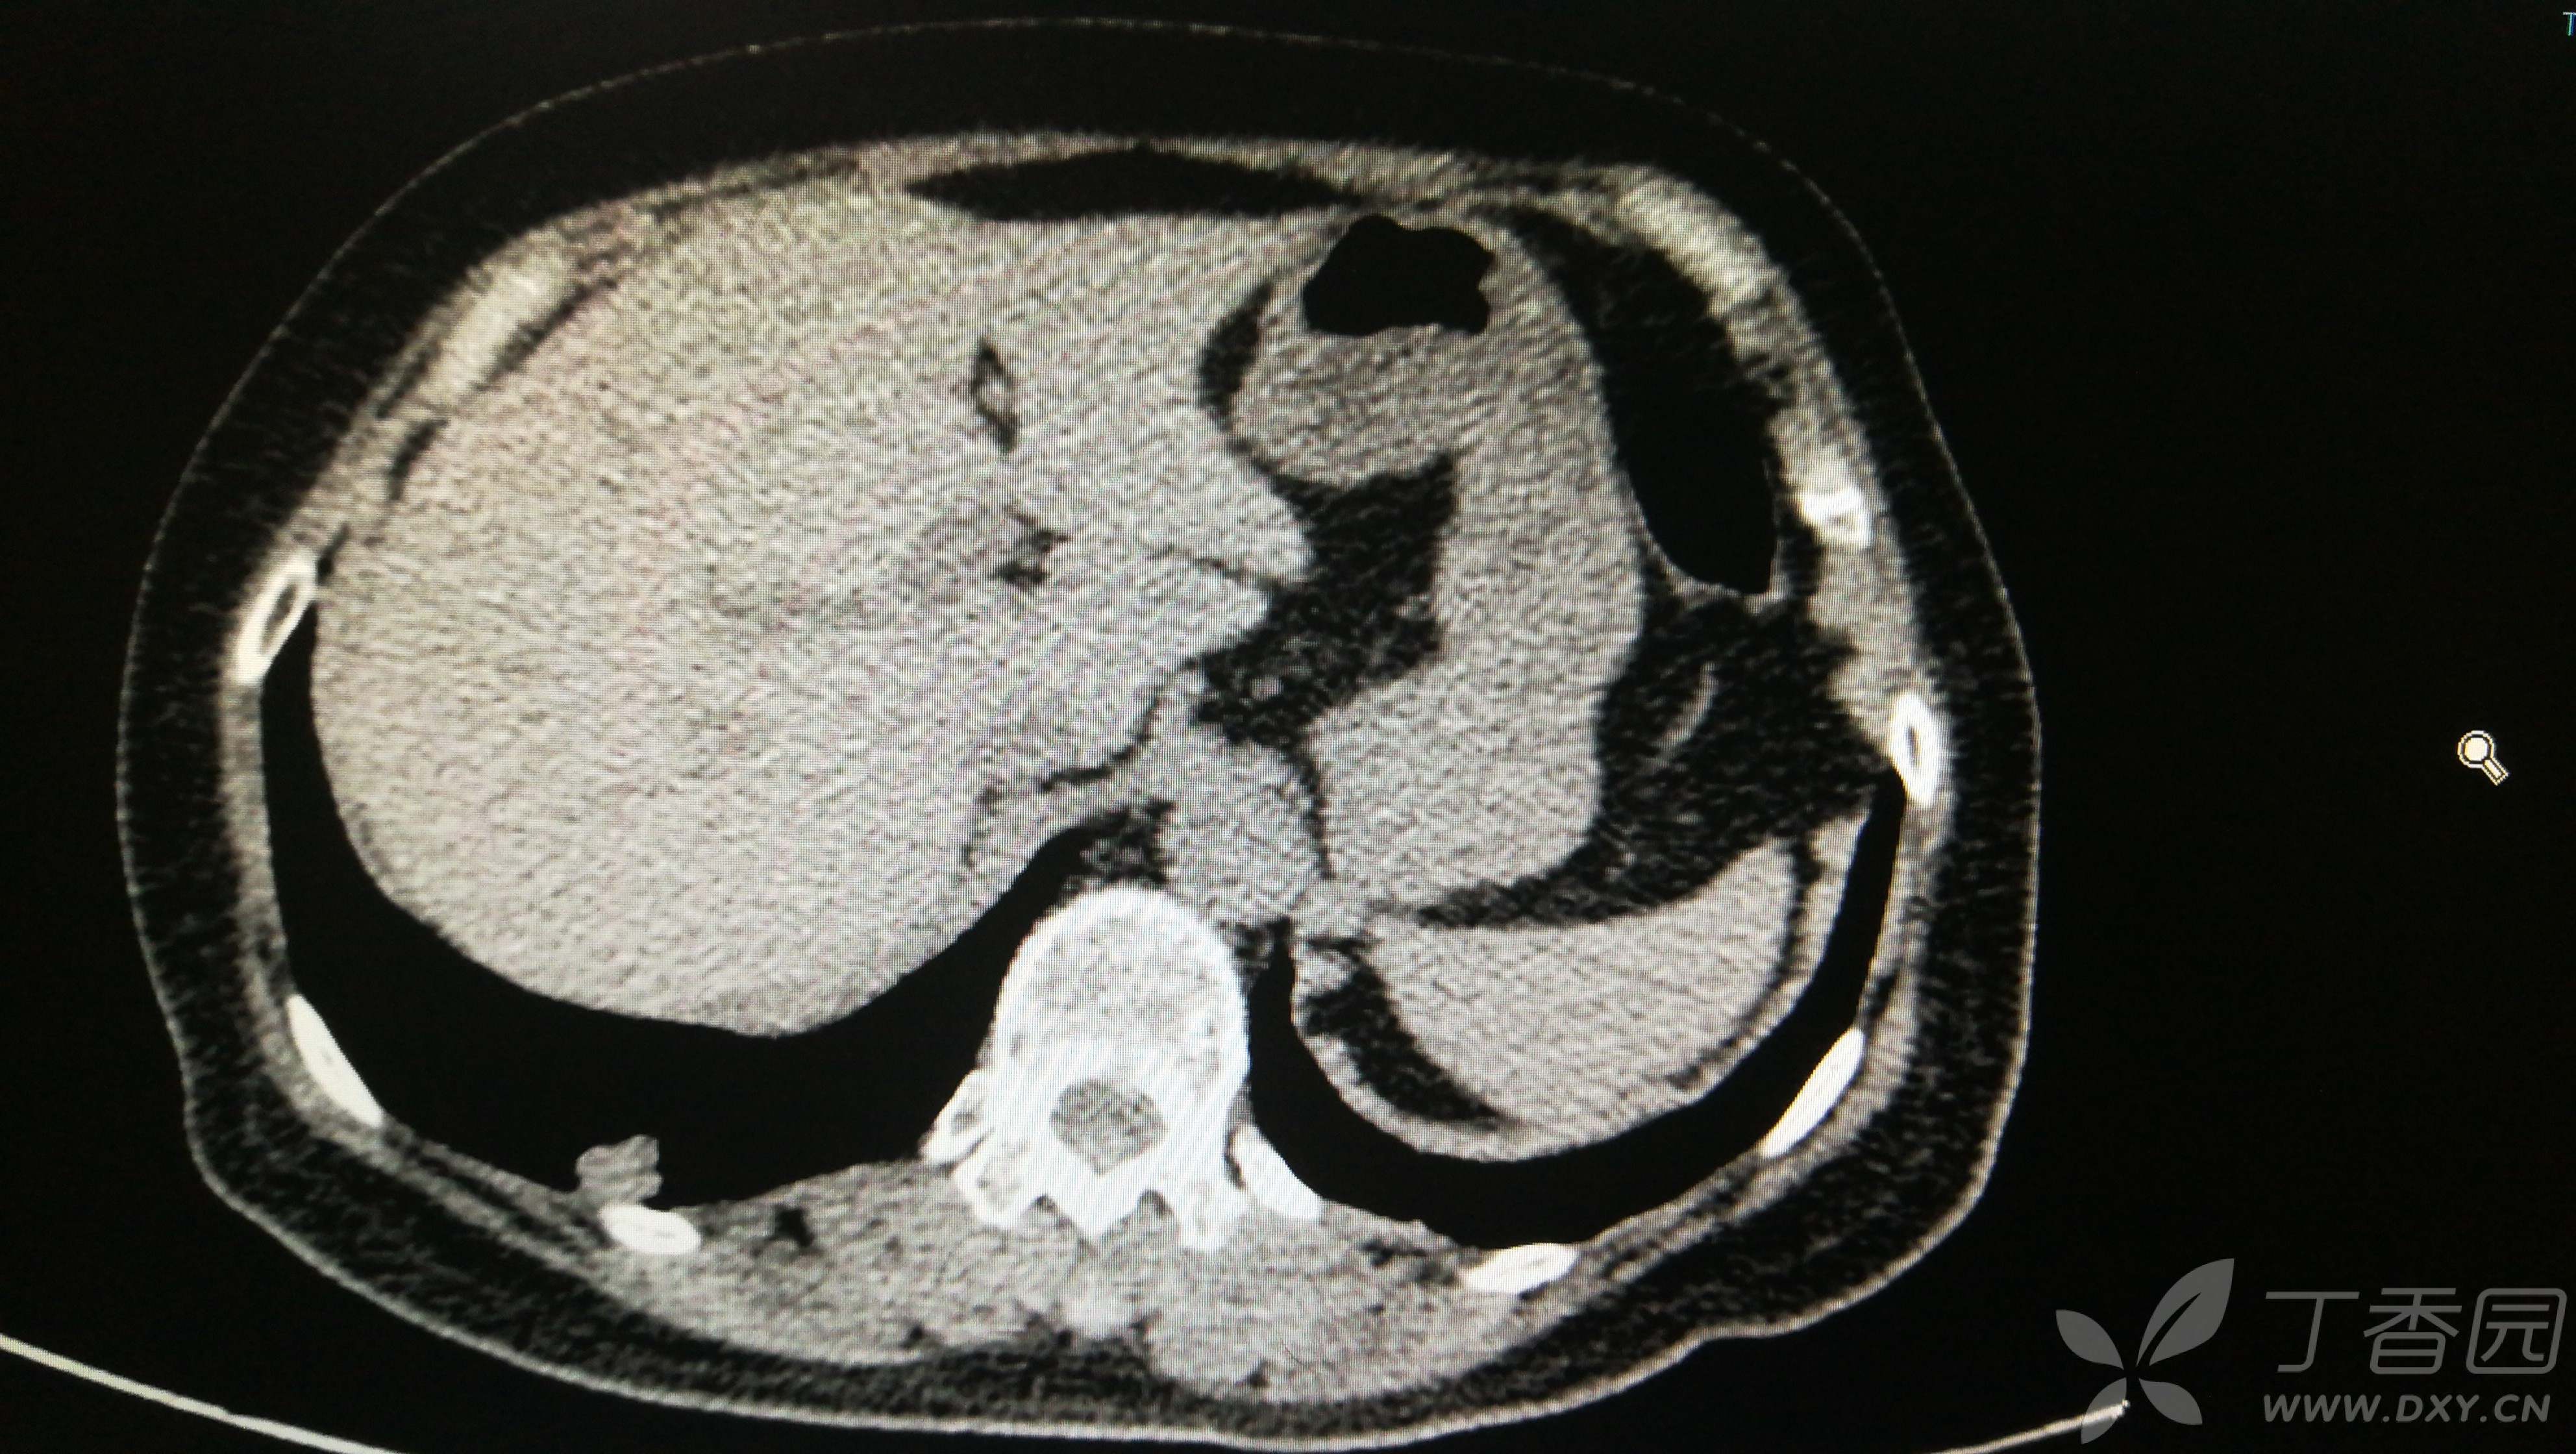

由于患者高龄,合并内科疾病,且肺部结节多发,其他部位检查未见明显肿瘤病灶。因此,手术行胸腔镜右下肺外后基底段切除+右上肺楔形切除术。